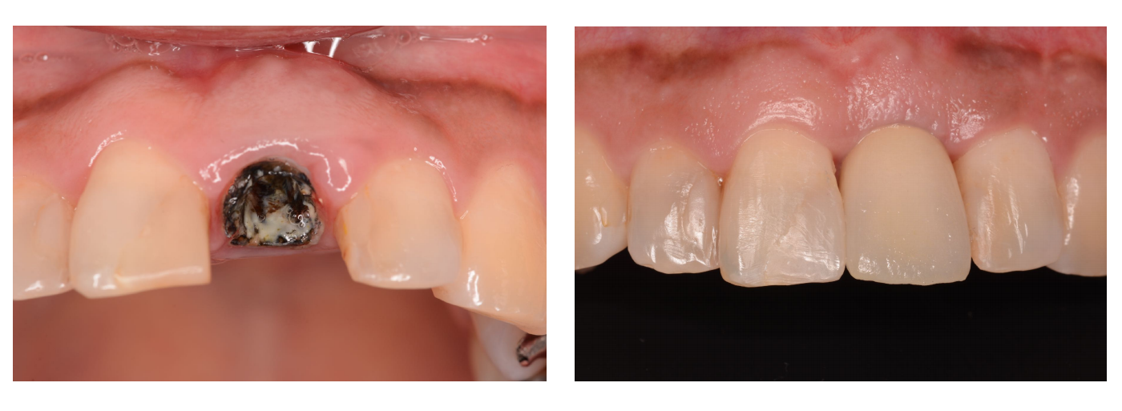

インプラント治療の症例4

(前歯の歯根破折)

| 診断名・主訴 | 左上1歯根破折 |

| 年齢 | 39歳 |

| 治療期間 | 1年間 |

| 治療内容 | インプラント治療 |

| 治療に用いた主な材料、設備機器 | 京セラFINESIAインプラント 上部構造:ジルコニアセラミック |

| 抜歯部位 | 左上1 |

| 治療費 | 約50万円 |

| リスク・副作用 | 術後出血や腫れ |